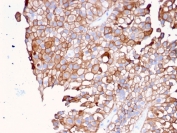

IHC staining of FFPE human urothelial carcinoma with UPK1B antibody. HIER: boil tissue sections in pH 9 10mM Tris with 1mM EDTA for 20 min and allow to cool before testing.